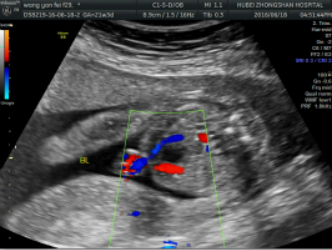

4.分娩前超声检查:超声重点观察指标包括:胎方位、胎儿大小、胎盘及胎儿循环、羊水量、胎盘成熟度、有无胎盘早剥或前置胎盘、脐带有无绕颈、脱垂等。这些指标对临产时医师选择正确的分娩方式,对母亲及胎儿健康平安至关重要。尤其对在整个孕期从未接受超声检查的准妈妈,为了母子的平安,分娩前务必接受一次超声检查。